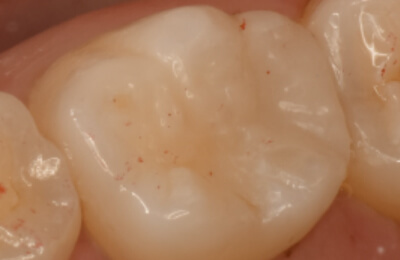

歯髄温存療法症例

術前

治療中

顕微鏡下でむし歯を除去

術後

レジン充鎮

矢印部に深いむし歯

封鎖性が良く、

組織の再生を促す

MTAセメントを充填 -

術後2年経過良好

| 主訴 | 冷たいものがしみる。 |

|---|---|

| 治療期間 | 歯髄温存療法1回 ダイレクトボンディング1回 |

| 治療費 |

|

| 治療内容 | マイクロスコープ下でむし歯の除去と、断髄(感染した死神経の一部を除去)を行い、歯髄保護材料(MTA)で封鎖して神経を保存。精密な修復治療により、歯の形態を回復した。 |

| 治療のリスク | 歯髄温存治療が奏効せず、歯髄炎または歯髄壊死になった場合は根管治療が必要になります。 |